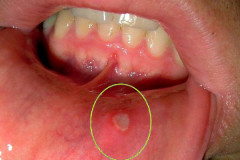

Ինչու՞ է առաջանում ստոմատիտ. ինչի՞ մասին այն կարող է վկայել